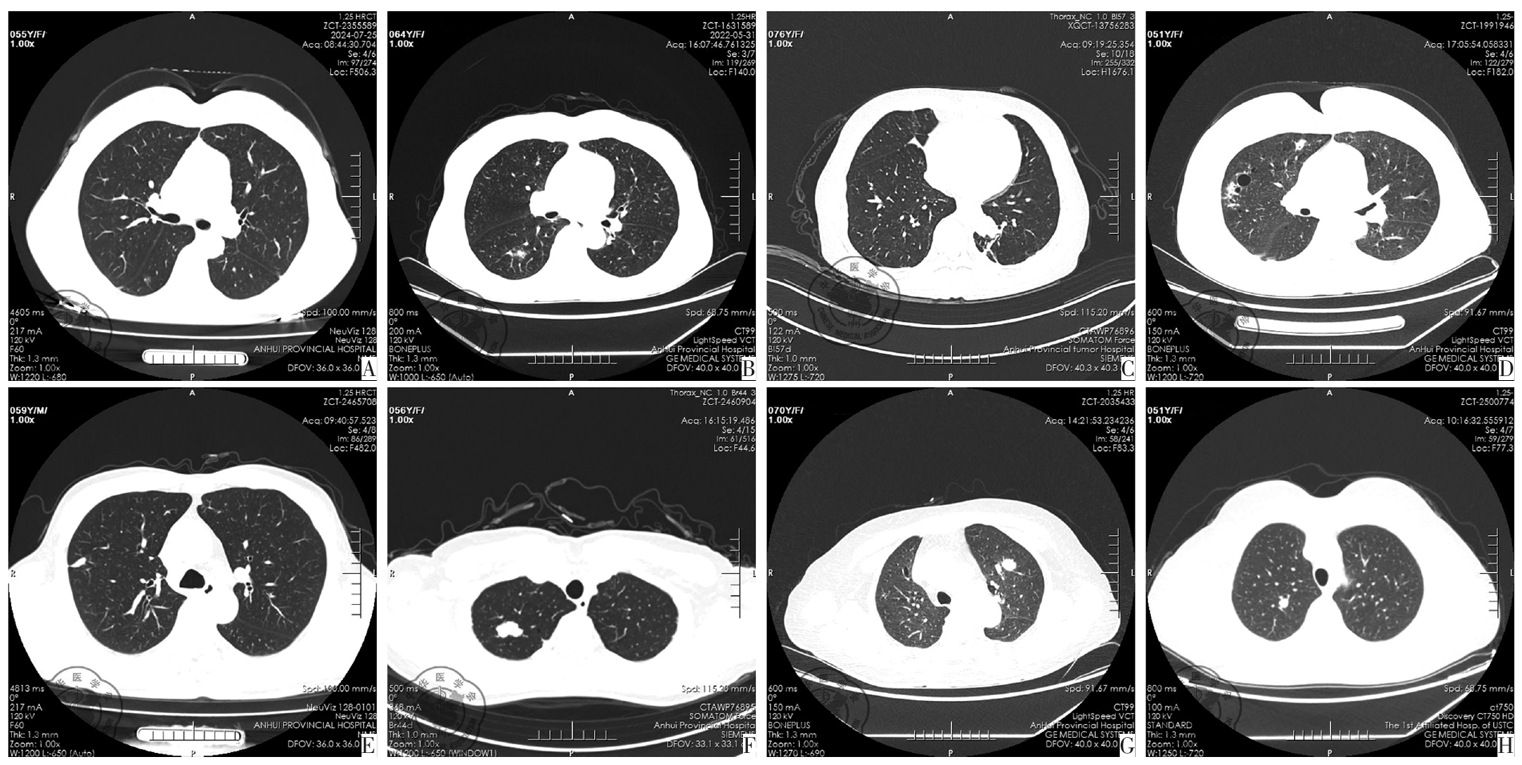

图1 pSS伴肺结节患者胸部CT扫描检查。图A为右肺下叶7 mm混杂磨玻璃结节,经手术肺活检诊断为微浸润腺癌;图B为右下肺边界欠清磨玻璃结节,经手术肺活检诊断为边缘区淋巴瘤;图C为左肺下叶分叶状结节影,局部包绕胸主动脉,病变区域支气管狭窄,经肺细针穿刺诊断为弥漫大B细胞淋巴瘤,生发中心源性;图D为双肺多发结节状高密度影,伴肺组织囊性变,经胸腔镜活检诊断为肺淀粉样轻链沉积;图E为右肺上叶一边界较清实性结节,18 mm×8 mm,经手术肺活检诊断为肉芽肿性炎;图F为右肺上叶不规则边界尚清高密度结节,可见分叶,23 mm×14 mm,其内可见点状钙化影,手术活检证实为纤维钙化结节;图G为左肺上叶类圆形高密度影,边缘见浅分叶,穿刺活检示多灶淋巴细胞、浆细胞浸润,并见较多碳末沉积;图H为右肺上叶类圆形高密度影,约10 mm,界清,经手术肺活检诊断为浆细胞瘤